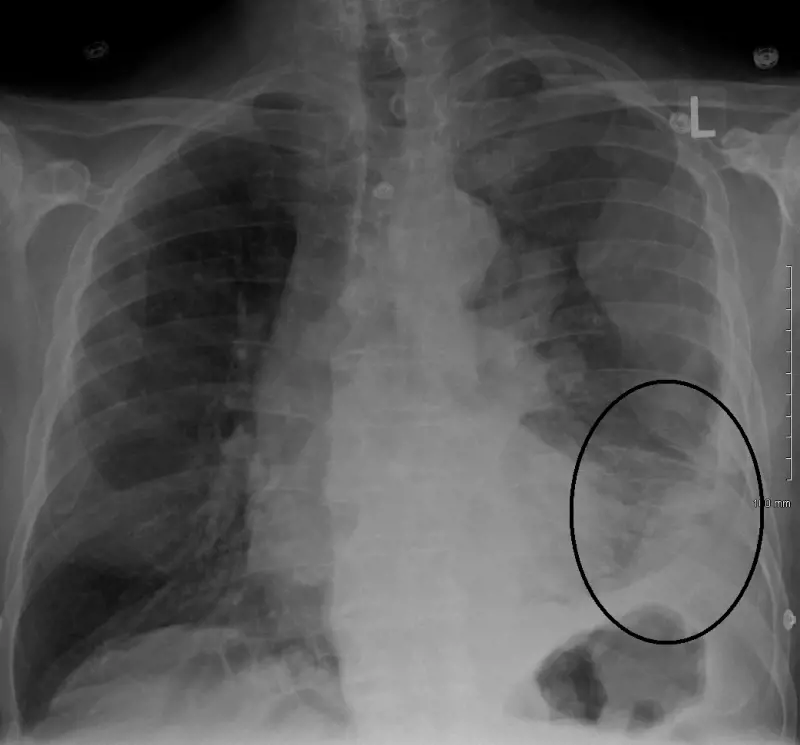

Intervistato da Fabio Fazio sul Nove e sul Corriere della sera, Franco Di Mare ha annunciato pubblicamente di aver contratto un mesotelioma. "Ho un tumore che non lascia scampo. Mi resta poco da vivere, quanto non lo so. Però non mollo. Confido nella ricerca", ha spiegato al quotidiano. Il mesotelioma è un tumore molto aggressivo che colpisce le cellule del mesotelio, ossia le membrane che rivestono gli organi interni. È un tumore non comune e quello del giornalista ha avuto origine nella pleura, la membrana dei polmoni. "Al posto del polmone destro c’era il nulla. Era collassato insieme alla pleura, la pellicola che lo avvolge. La cassa toracica per metà era vuota", ha detto ancora.

Il mesotelioma pleurico che ha colpito Di Mare è rappresentativo di 4 casi su 5 di questo tipo di tumore. Ma rientrano in statistica anche il mesotelioma peritoneale, mesotelioma pericardico e mesotelioma della tunica vaginale, ma sono tutti molto rari. Il mesotelioma pleurico inizia a manifestarsi con l'insorgenza di liquido nella cavità pleurica, che rende il fiato corto e provoca tosse. A questi si aggiungono successivamente dolori e debolezza e, purtroppo, quando viene diagnosticato è già in uno stadio avanzato che non permette la guarigione. La ricerca non si ferma e sono stai fatti importanti passi in avanti, che offrono a chi ne soffre un allungamento dell'aspettativa di vita.